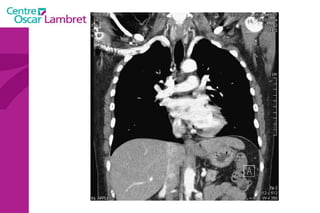

L’appareil circulatoire L’ aorte  est la plus grande artère du corps.  Elle part du ventricule gauche du coeur et apporte notamment du sang oxygéné à toutes les parties du corps via la circulation. Elle est divisée en aorte thoracique et aorte abdominale. L’aorte thoracique  comprend trois segments : l'aorte ascendante, horizontale et descendante.

L’aorte ascendante  : L’aorte ascendante constitue le segment initial de l’aorte, elle fait 27 mm de diamètre et émerge du VG, dont elle est séparée par la valve aortique. Cette portion fait 6 cm de hauteur, divisé en deux régions: le sinus de Valsalva, fortement dilaté, oblique en avant.  le grand sinus aortique, dilaté, jusqu'à la portion horizontale de l’aorte.  L’appareil circulatoire

La  crosse de l’aorte  ou aorte horizontale :  L’aorte horizontale passe ensuite derrière l’artère pulmonaire et la bronche souche gauche. Trois vaisseaux naissent de cette crosse aortique: le tronc brachio-céphalique, l’artère carotide primitive gauche, et l’artère sous-clavière gauche. Ces vaisseaux irriguent la tête et les membres supérieurs. L’appareil circulatoire

L’aorte descendante  : L’aorte descend ensuite dans le médiastin, en arrière du cœur et en avant de l’oesophage dans sa partie supérieure, en arrière dans sa partie inférieure. Cette partie est relativement fixée par rapport aux deux autres segments. La jonction entre l’aorte horizontale et descendante est appelée isthme   aortique.  Elle traverse ensuite le diaphragme et devient l’aorte abdominale. L’appareil circulatoire

L’aorte initiale ou segment 0 L’aorte ascendante ou segment I  qui lui fait suite, constitue la partie initiale de la crosse aortique . Sa longueur est d'environ 6 à 7 cm. Le segment II  est représenté par la partie horizontale de la crosse aortique . Le segment III  est l’aorte thoracique descendante. Le segment IV  est la région de l’aorte qui est située sous le diaphragme  Le segment V  est la partie sous rénale de l’aorte  L'aorte